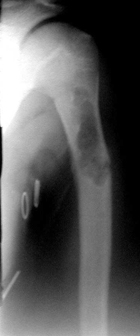

С момента внедрения в клиническую практику ДКИ разной степени деминерализации, выполненных по технологии ЦИТО, прошло более 12 лет. За это время значительному ко-личеству больных были произведены реконструктивные операции с помощью костно-пластического материала «Перфоост» [13]. Результаты лечения и сроки органотипического восстановления значительных объемов костной ткани в области аллопластики позволили утверждать, что разработанные в тканевом банке ЦИТО ДКИ безопасны и обладают высокими остеоиндуктивными свойствами [5]. Адекватное количество пластического материала, его разные формы и прочностные характеристики способствовали полному заполнению пострезекционных дефектов (рис. 1, 2).

| Рисунок 1. Больная Р. 12 лет. Солитарная киста верхней трети левой плечевой кости: | ||

| а) рентгенологическая картина состояния до операции; | б) через 4 месяца после пластики дефекта пластинами ДКИ «Перфоост»; | в) через 11 месяцев после проведенной операции. |